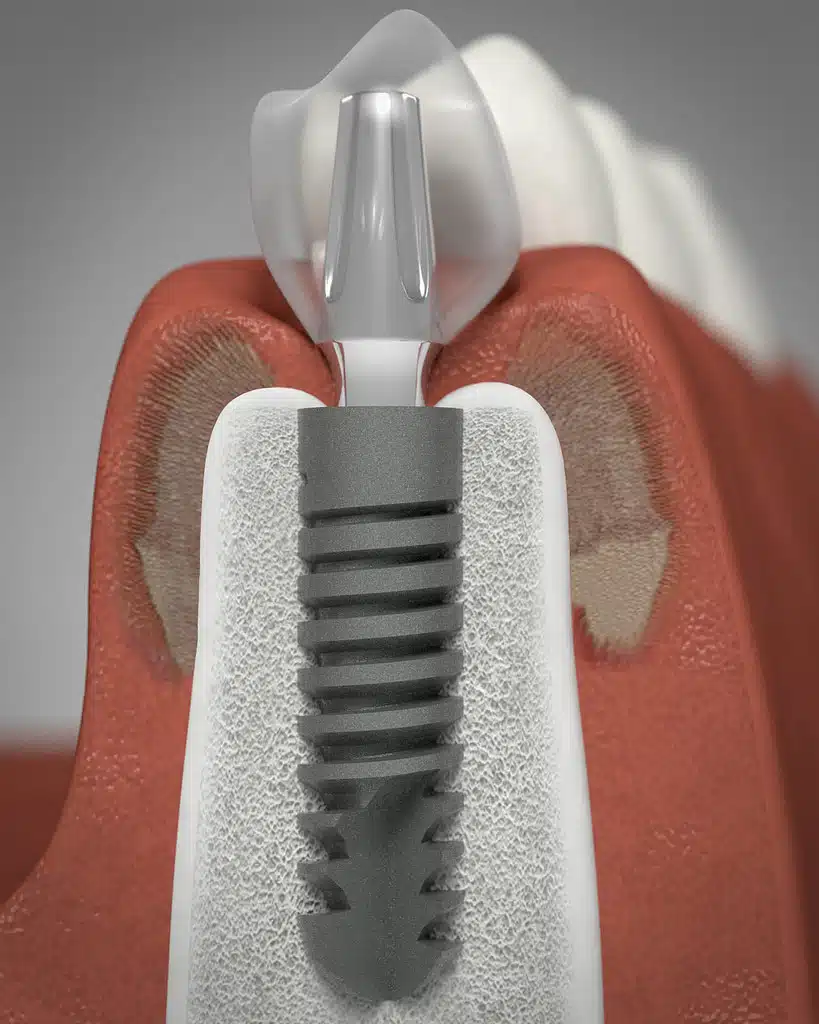

Implantes Dentales

Siempre realizado por un implantólogo especializado o periodoncista. Los implantes dentales son la mejor opción para reemplazar los dientes perdidos, ya sea un diente que falta o un arco completo. En realidad, el procedimiento de implante dental no es tan complejo como muchas personas creen y no es un procedimiento doloroso en absoluto. La colocación de un implante puede realizarse en aproximadamente 30 minutos o menos.

Un implante dental es un tornillo especial que reemplaza la raíz de un diente que falta. Una vez colocado, el implante requiere tres meses para asentarse en el hueso de la mandíbula. Luego, la etapa final requiere dos cosas; un pilar (conector) y la corona.